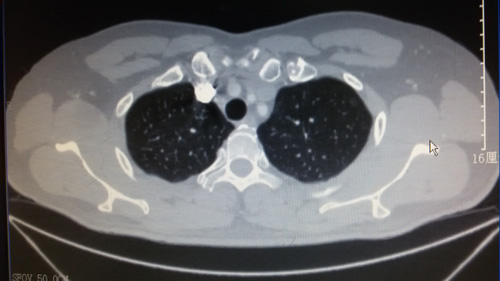

50歲的楊某體檢時發(fā)現(xiàn)左上肺一純磨玻璃結(jié)節(jié),大小約0.6×0.7cm,此病灶CT薄層掃描下方可看清,病灶厚度僅有不到一個層面。患者治療意愿強烈,慕名到市醫(yī)院并入住胸心外科。

胸心外科林建生主任、關(guān)軍副主任醫(yī)師、許建新主治醫(yī)師、陳信淳主治醫(yī)師組成的醫(yī)療小組,經(jīng)反復的術(shù)前討論及研究,決定給予術(shù)前行微彈簧圈Microcoil定位并微創(chuàng)手術(shù)切除。該患者術(shù)后復查胸部CT左肺恢復良好,術(shù)后病理提示為TisN0M0,原位癌。